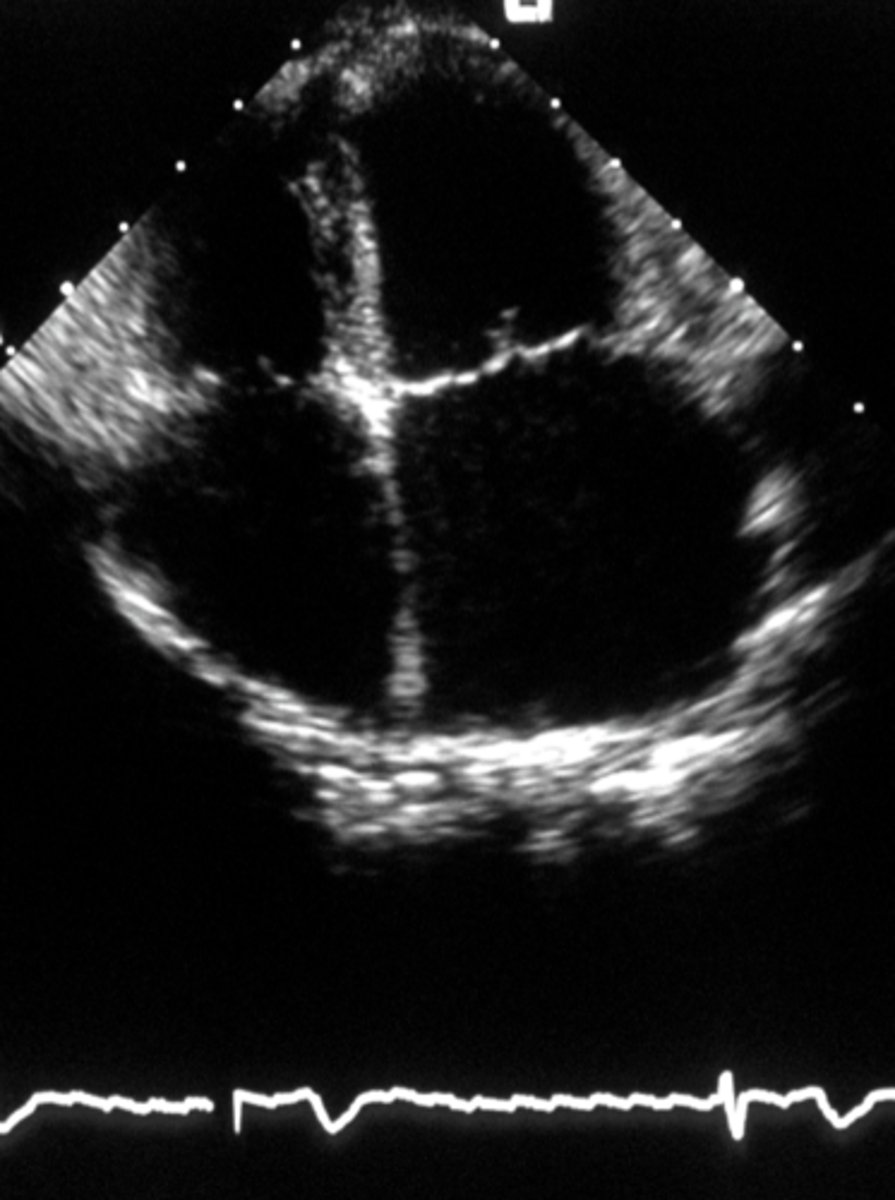

What does the parasternal short axis view look like at the level of the mitral valve?

fish mouth